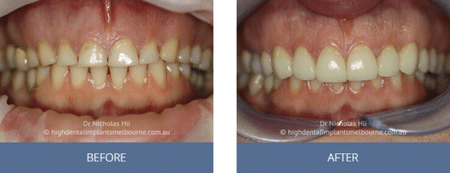

Clinical Before and After Photos

At High Dental, we believe a great smile changes everything. Our Smile Gallery showcases before-and-after images of patients who trusted us with their smiles. From veneers and crowns to full-arch implants, each result is unique — and each started with a consultation. Scroll through and imagine the possibilities for your own smile.

Images are provided for illustrative purposes only. Results shown relate to specific patients and individual outcomes may vary. A consultation is required to determine suitability for treatment.